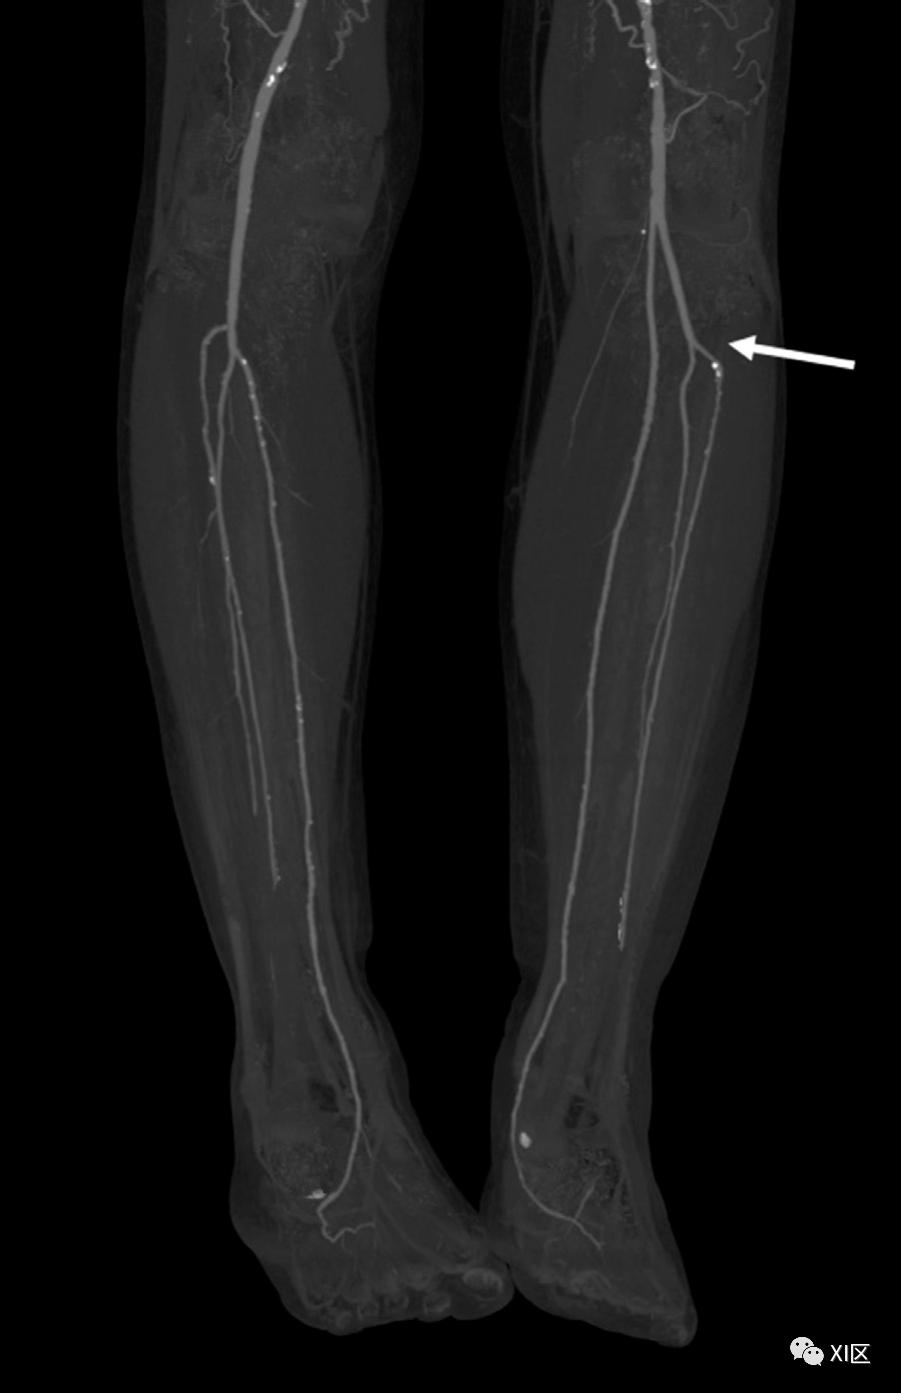

图2 31岁,解剖结构正常。冠状位上膝关节下方的最大密度投影CTA图像显示腘动脉(1)分叉成胫腓干(2)和胫前动脉(3)。胫腓干进一步分为胫后动脉(4)和腓动脉(5)。据报道,11.3%的患者在CTA上看到腘动脉的分支模式变异。腘动脉分支最常见的变异是胫前动脉的高位起源(图3),胫前动脉和腓动脉的共同起源(图4),所有三个分支都在5mm内分叉的三叉,以及胫后动脉发育不良或再生不良。腓动脉在踝部终止于由前部和后部穿孔分支形成的分叉处。95%的人胫前动脉和胫后动脉继续进入足部。5%的人存在一个变异,就是没有这些径流血管之一,而有一个腓动脉可能继续到足部。

图3 52岁女性,胫前动脉高分支。冠状位上的最大密度投影CTA图像显示了左腿胫骨平台水平处胫前动脉的高分支(箭头)。相比之下,右胫前动脉的分支在右腿上处于正常水平。

图4 冠状位最大密度投影CTA图像显示,65岁男子左腿胫前动脉和腓动脉源自同一起源(箭头)。足部的动脉供应高度可变。经典的足部血管解剖学是由两条循环通路组成,通过足弓连接。前循环由胫前动脉提供,因为它变成了足背动脉(直径为1.9-2.0mm),通过足底深支供应足弓。后循环由胫后动脉和腓动脉的分支组成,产生内侧和外侧足底动脉,以及小腿内侧动脉。足外侧动脉和足深动脉通常吻合形成足弓。足弓产生了跖动脉和足底指动脉,为脚趾提供血液供应。